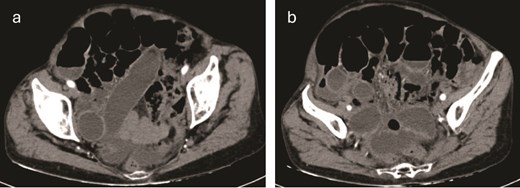

Contrast-enhanced computed tomography (CT) of the abdomen revealed loops of small intestine with dilation up to 31 mm and the presence of a whirl sign at the level of the distal ileum associated with a transition zone. Sigmoid diverticulosis and free fluid in the peritoneal cavity were noted, distributed in the anterior subhepatic space, both paracolic gutters, and scantily among intestinal loops. Imaging suggested considerations of a midgut volvulus versus adhesions in the topography of the distal ileum (Fig. 1 a and b).

(a, b) Contrast-enhanced CT of the abdomen revealed loops of small intestine with dilation up to 31 mm and the presence of a whirl sign at the level of the distal ileum associated with a transition zone.